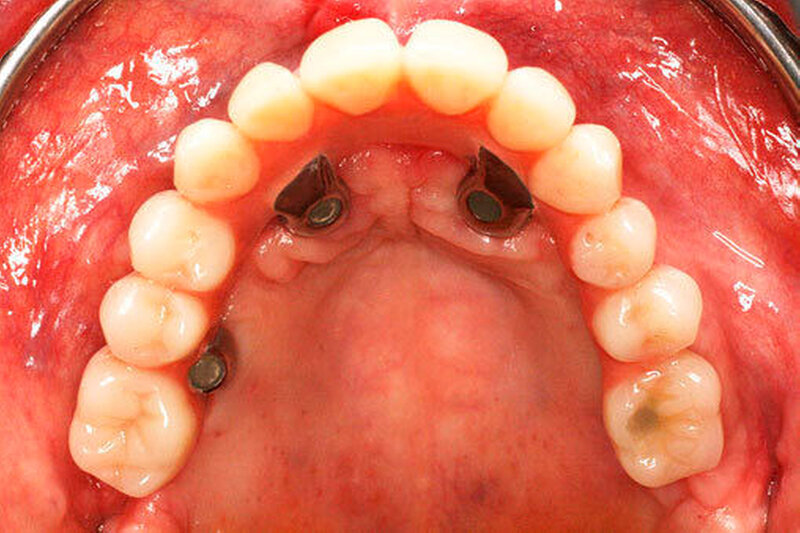

Bei der Sofortversorgung nach dem All-on-4 Konzept (Abbildung 1a-d) werden die frontalen Implantate gerade inseriert und axial belastet, die distalen in der Regel anguliert (Abbildung 2). Durch die Angulation kann ein externer Sinuslift im Oberkiefer umgangen und eine ausreichende Primärstabilisation für eine Sofortversorgung erreicht werden. Im Unterkiefer verhindert das Foramen mentale bei gerader Insertion häufig eine dorsale Positionierung der Implantate. Durch die Angulation der distalen Implantate werden das Belastungspolygon optimiert und ausgeprägte distale Cantilever (Extensionsbrücken) vermieden.

Entscheidend für den Erfolg dieses Konzepts ist die Hygienefähigkeit des Zahnersatzes. Die Basis des Zahnersatzes sollte konvex gestaltet werden und nur linear zum Kieferkamm Kontakt haben (Abbildung 1d). Diese Gestaltung erleichtert eine einfache Mundhygiene mit Interdentalbürsten und Zahnseide. Die Hygienefähigkeit einer All-on-4 Konstruktion ist somit vergleichbar mit einer Stegversorgung. Entscheidend für die Ästhetik ist die präoperative Feststellung der Lippenlachlinie. Diese entscheidet über die Resektionshöhe des Kieferkamms. Die Ästhetik wird bei dieser Versorgungsart ausschließlich über den Zahnersatz erreicht (Abbildung 1d). Die „rote Ästhetik“ kann durch die Verwendung von Prothesenkunststoff individuell und natürlich gestaltet werden. Der Zahnersatz ist bei diesem Konzept okklusal mit den Implantaten verschraubt (Abbildung 1c). Bei Notwendigkeit, zum Beispiel bei Reparaturen, kann dieser durch den Behandelnden leicht ab- genommen werden.

Eine erhebliche Erweiterung der Indikation des All-on-4 Konzeptes konnte durch den Einsatz von Zygoma-Implantaten erzielt werden. Zygoma-Implantate werden im Os zygomaticum verankert und erreichen auch in Situationen mit starker Kieferkammatrophie eine hohe Primärstabilität. Herkömmliche augmentative Verfahren können so vermieden werden. Zygoma-Implantate wurden zunächst bei Patienten mit besonderen Dysplasien im Kieferbereich und bei Tumorpatienten nach Resektion von Kieferanteilen eingesetzt. Balshi war einer der ersten Kliniker, der mit speziell gestalteten Implantaten entsprechende Fälle versorgte. Die Übertragung des All-on-4 Konzeptes auf Zygoma-Implantat-getragene Versorgungen ist insbesondere mit dem Namen Malavez verbunden, die sich sehr um diese Technik verdient gemacht hat. Dieses Konzept auf Zygoma-Implantaten wird angewendet in Fällen mit ausgeprägter Kieferkammatrophie im Oberkiefer (Abbildung 4a). Die Zygoma-Implantate werden in aller Regel in ITN inseriert. Lediglich ein externer Sinuslift ist als augmentative Maßnahme notwendig (Abbildungen 4b und c). Durch dieses Vorgehen können aufwändige augmentative Verfahren umgangen werden. Die prothetische Versorgung der Zygoma-Implantate entspricht dem Vorgehen wie beim All-on-4 Konzept und erfolgt einen Tag postoperativ. Erreicht wird, wie beim ursprünglichen All-on-4 Konzept, eine festsitzende Sofortversorgung (Abbildungen 3 und 4d).